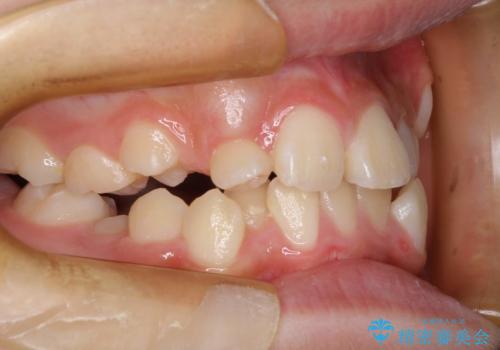

永久歯が生えてこない ワイヤー矯正で複雑な状態を正常咬合へ誘導する

- 乳歯の晩期残存による永久歯の萌出遅延・過剰歯・萌出異常

など多くの問題を抱えていた。

乳歯がうまく抜けず、過剰歯が存在していたことにより、永久歯が位置異常をおこし、非常に複雑な状況となってしまっていました。